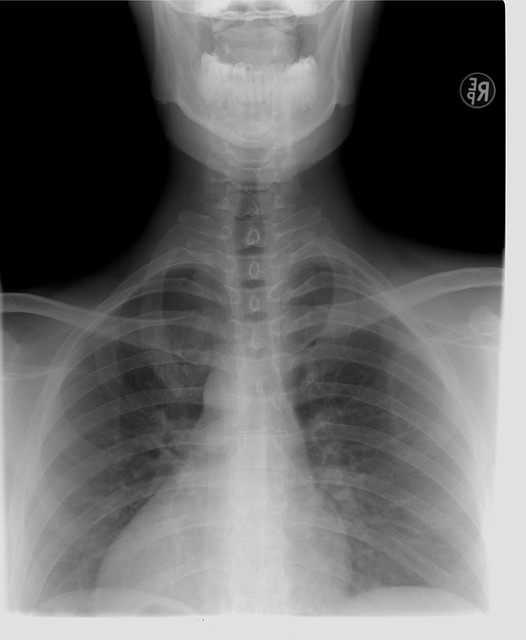

갈비뼈 연골염은 신체 검사와 영상 검사를 통해 진단할 수 있어요.

- 신체 검사: 눌렀을 때 압통이 있는지 확인해요.

- X-ray 검사: 다른 골절이나 폐 질환과 감별하기 위해 시행될 수 있어요.

- CT 또는 MRI 검사: 심한 염증이 있을 경우 연골 상태를 정밀하게 확인할 수 있어요.

- 심전도(EKG): 심장 질환과 감별하기 위해 시행될 수 있어요.